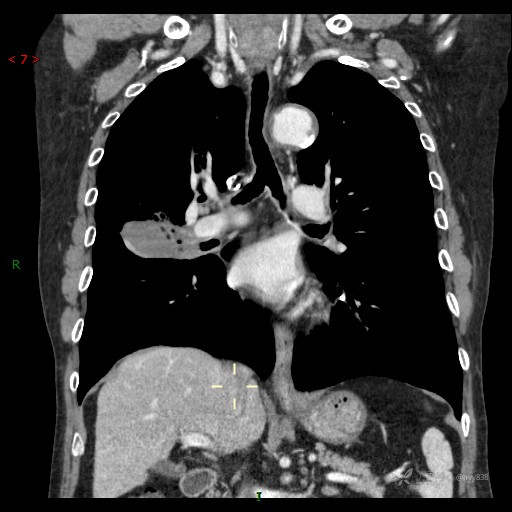

大叶性分布并低密度坏死改变,结核?真菌?肿瘤?有时候很难界定---结果公布~

讨论:影像特征?病变性质?

胸部CT肺窗